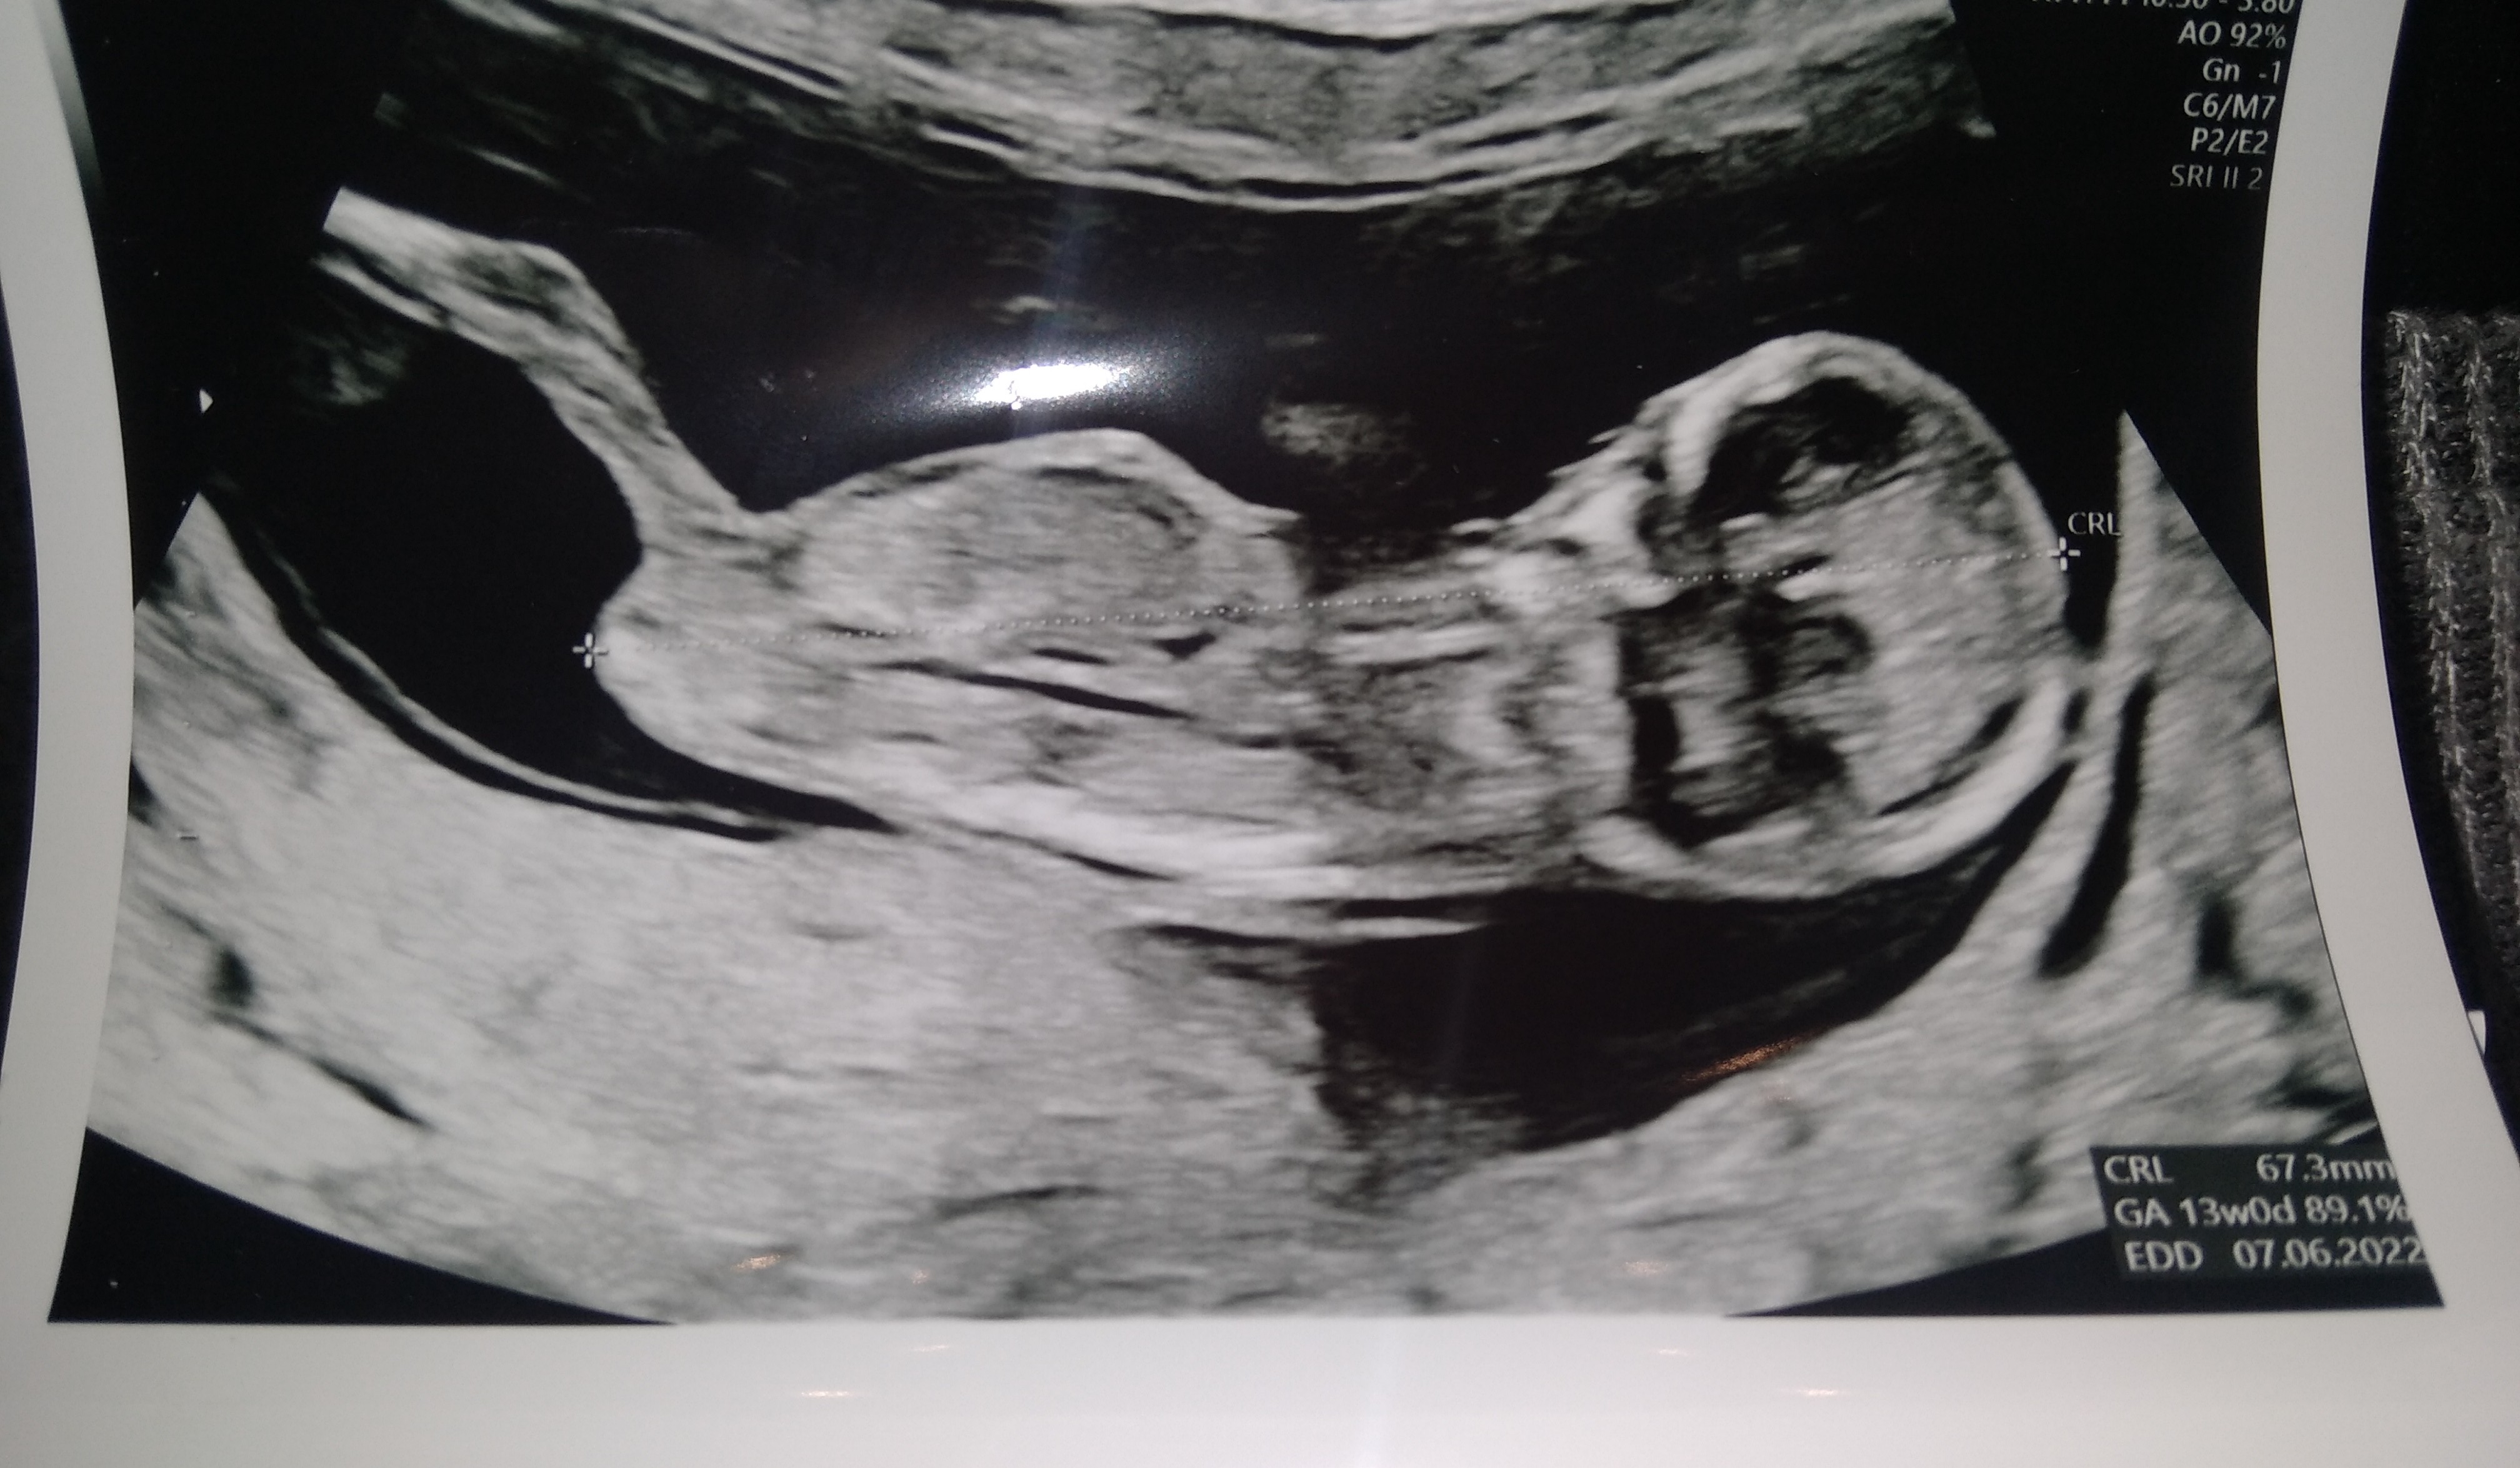

ojej jakie wiadomości. A ja jestem po prenatalnych. Z USG 13+0, rośnie zdrowy maluszek 😍

Załączniki

• IMG_20211130_185531.jpg

IMG_20211130_185531.jpg

1 MB · Wyświetleń: 142